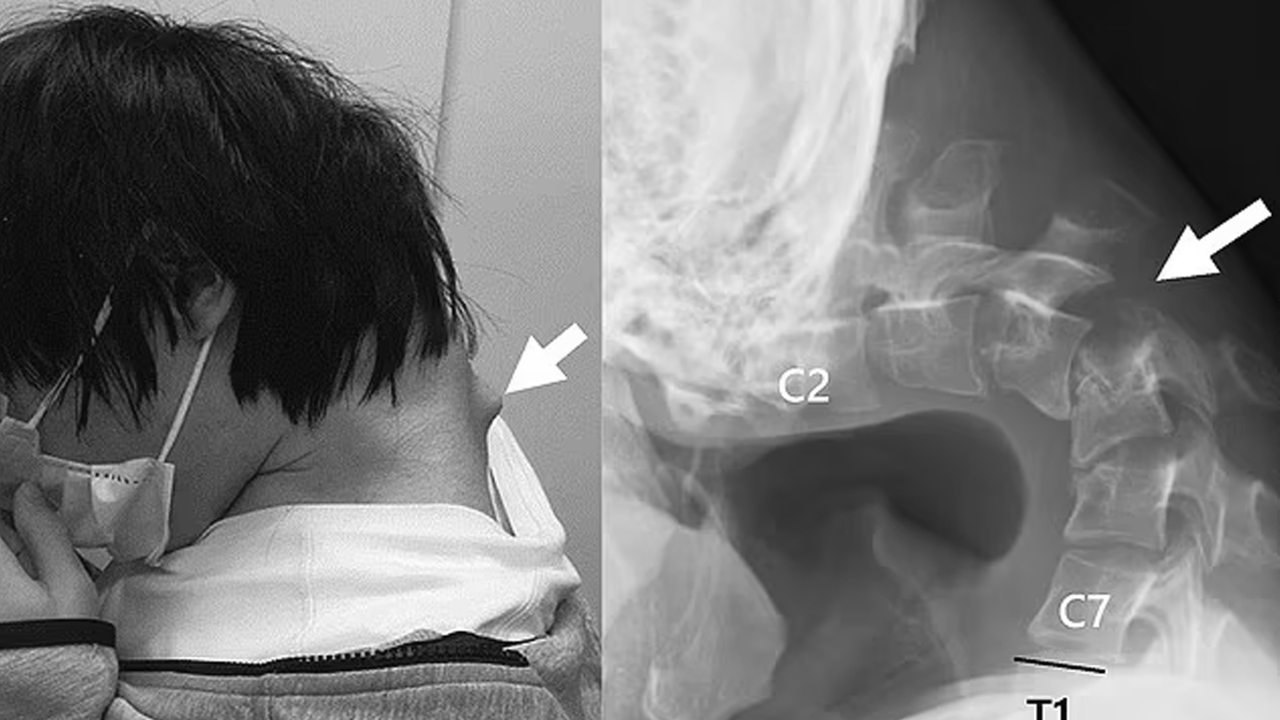

因长时间低头玩手机,日本25岁男子颈部肌肉萎缩,颈椎变形错位

图片尺寸1280x720